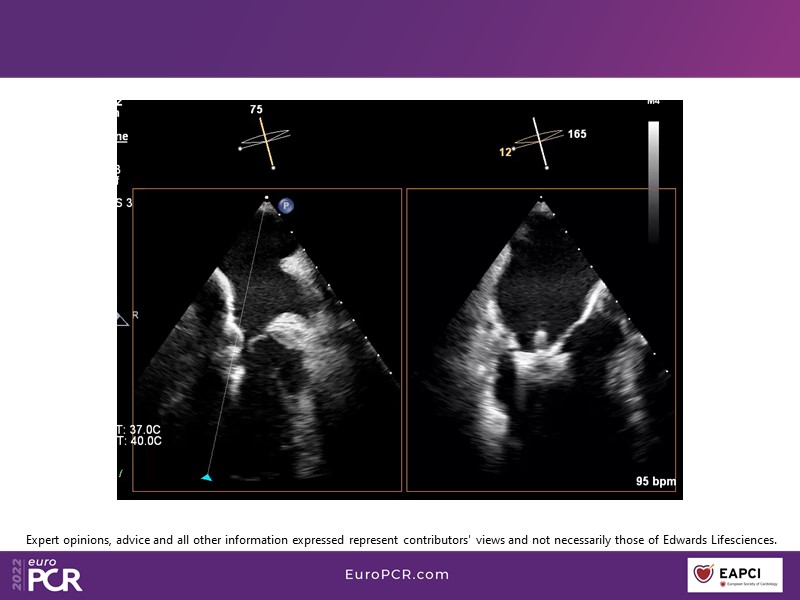

With study outcomes and clinical cases, this EuroPCR 2022 session will enable you to discuss the anatomical considerations that define suitable candidates for treatment of mitral regurgitation with the PASCAL platform and highlight key differentiators and tips and tricks for its use.

- To discuss which anatomical considerations define suitable candidates for the treatment of mitral regurgitation with the PASCAL platform

- To attend case-based discussions that will highlight key differentiators and tips and tricks when using the PASCAL platform to treat mitral regurgitation